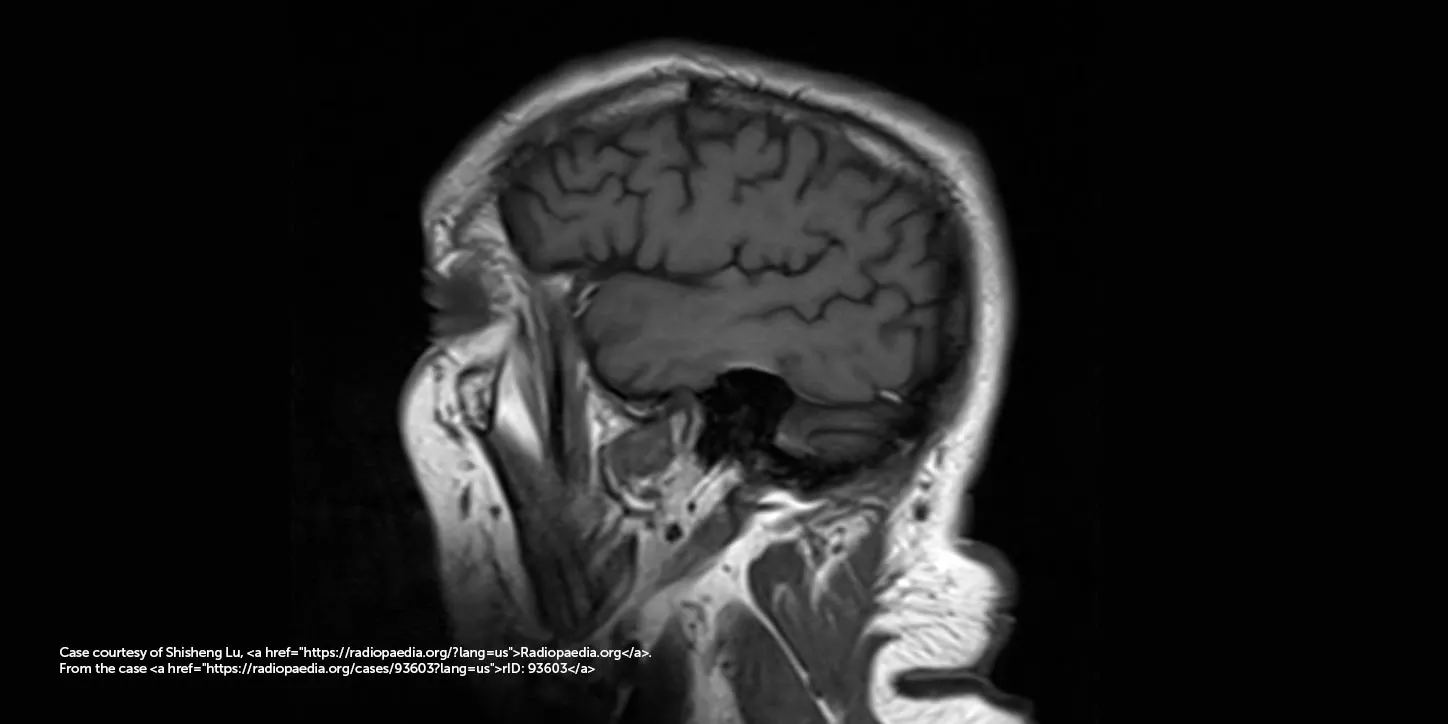

O diagnóstico da DCL é clínico, feito por neurologistas especializados, mas pode ser apoiado por exames:

- Ressonância magnética (RM) e tomografia (TC): para descartar outras causas de demência e avaliar alterações estruturais.